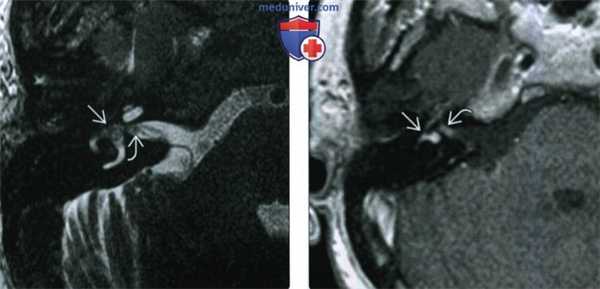

(Слева) При аксиальной МРТ Т1ВИ определяется минимальный гиперинтенсивный сигнал в преддверии и улитке у пациента с вестибулокохлеарной шванномой.

(Справа) При аксиальной MPT Т2ВИ визуализируется материал с сигналом, соответствующим мягким тканям, замещающий сигнал, типичный для нормальной жидкости в преддверии и улитке у пациента с ИЛШ вестибулокохлеарного типа. Эти опухоли чаще распознаются на МРТ высокого разрешения (Т2) в условиях высокой настороженности.

(Слева) При аксиальной МРТ Т2 ВИ определяется ИЛШ трансмакулярного типа в виде материала с интенсивностью сигнала, соответствующей мягким тканям, заполняющего преддверие и распространяющегося вдоль ветвей преддверного нерва до дна дистальных отделов внутреннего слухового канала (ВСК).

(Справа) При аксиальной МРТ Т1ВИ у этого же пациента определяется контрастное усиление интравестибулярной и дистальной интраканаликулярной части этой трансмакулярной шванномы. Минимальное отличие параметров контрастного усиления обусловлено эффектом усреднения объема.